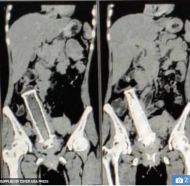

وعندما أجرى الأطباء فحصًا بالأشعة السينية، اكتشفوا جسمًا كبيرًا غريبًا داخل رحمها، قبل أن تؤكد الأشعة المقطعية وجود جزء من مقبض دراجة نارية يبلغ طوله 15 سم، في رحمها وأمعائها الدقيقة ومثانتها.

ومن ثم أجرى فريق من 19 طبيبًا عملية جراحية لإزالة رحمها المتضرر للغاية. وقالت الدكتورة ”سونيا موسى“: ”لقد أخبرتنا المريضة أن زوجها أدخل المقود في مهبلها عندما كانا في حالة سكر، ثم هددها بأذيتها إذا اخبرت أي أحد“.

وشرحت: ”ظل الجسم الغريب بداخلها لمدة عامين، حتى أصابها بعدوى شديدة تسببت في تآكل أعضائها، وتركتها في ألم مبرح“.

ولحسن الحظ تمكن الأطباء من إصلاح مثانتها بتثبيت دعامة في أنبوبها البولي، ولكنها لن تستطيع إنجاب المزيد من الأطفال.